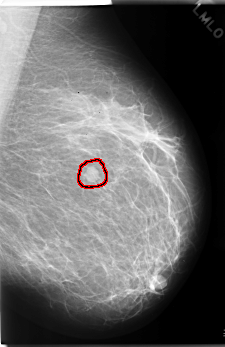

C_0164_1.RIGHT_MLO

LEFT_MLO LINES 5888 PIXELS_PER_LINE 3816 BITS_PER_PIXEL 12 RESOLUTION 50 OVERLAY

FILE: C_0164_1.LEFT_MLO.OVERLAY

TOTAL_ABNORMALITIES 1

ABNORMALITY 1

LESION_TYPE MASS SHAPE OVAL MARGINS CIRCUMSCRIBED

ASSESSMENT 4

SUBTLETY 5

PATHOLOGY MALIGNANT

TOTAL_OUTLINES 1

BOUNDARY